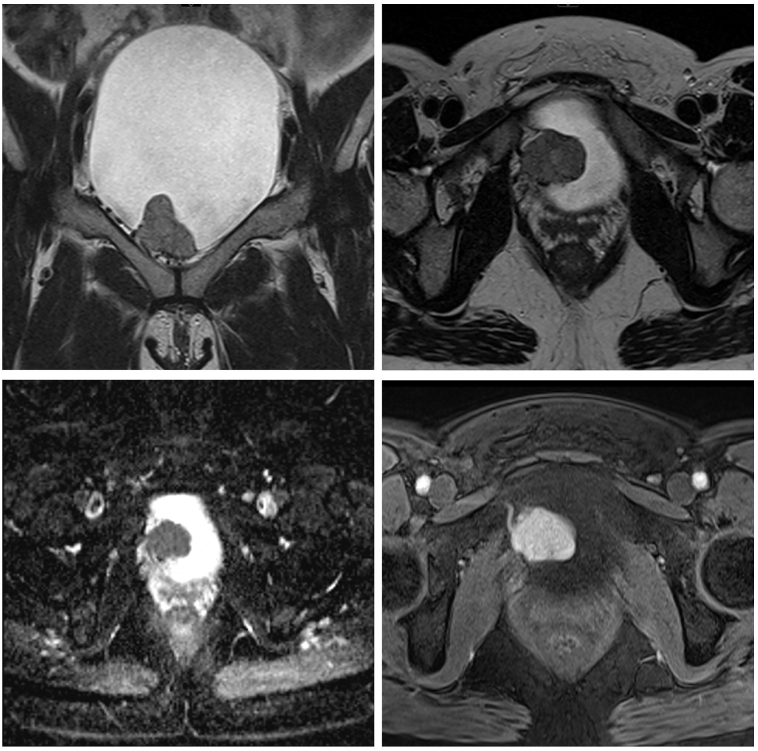

Bladder paragangliomas are rare extra-adrenal urological tumors that account for around 0.05% of bladder cancers. Their diagnosis is often delayed because of the rarity of these tumors. There is a risk of an intraoperative hypertensive crisis if not diagnosed or identified before surgical removal. We describe a case of a 36-year-old lady presented with a 10-year history of post-micturition palpitations and headaches. Her biochemical workup showed raised urinary normetanephrine levels and imaging showed a 123I MIBG-avid bladder mass compatible with bladder paraganglioma, although interestingly almost no tracer was picked up in 68Ga DOTATATE imaging. She was started on phenoxybenzamine to control her blood pressure prior to surgery. She underwent a successful robotic partial cystectomy with no complications. After surgery, she remained symptom-free. Bladder paragangliomas are rare neuroendocrine tumors of the bladder, which need to be diagnosed and managed effectively to avoid intraoperative and long-term complications.